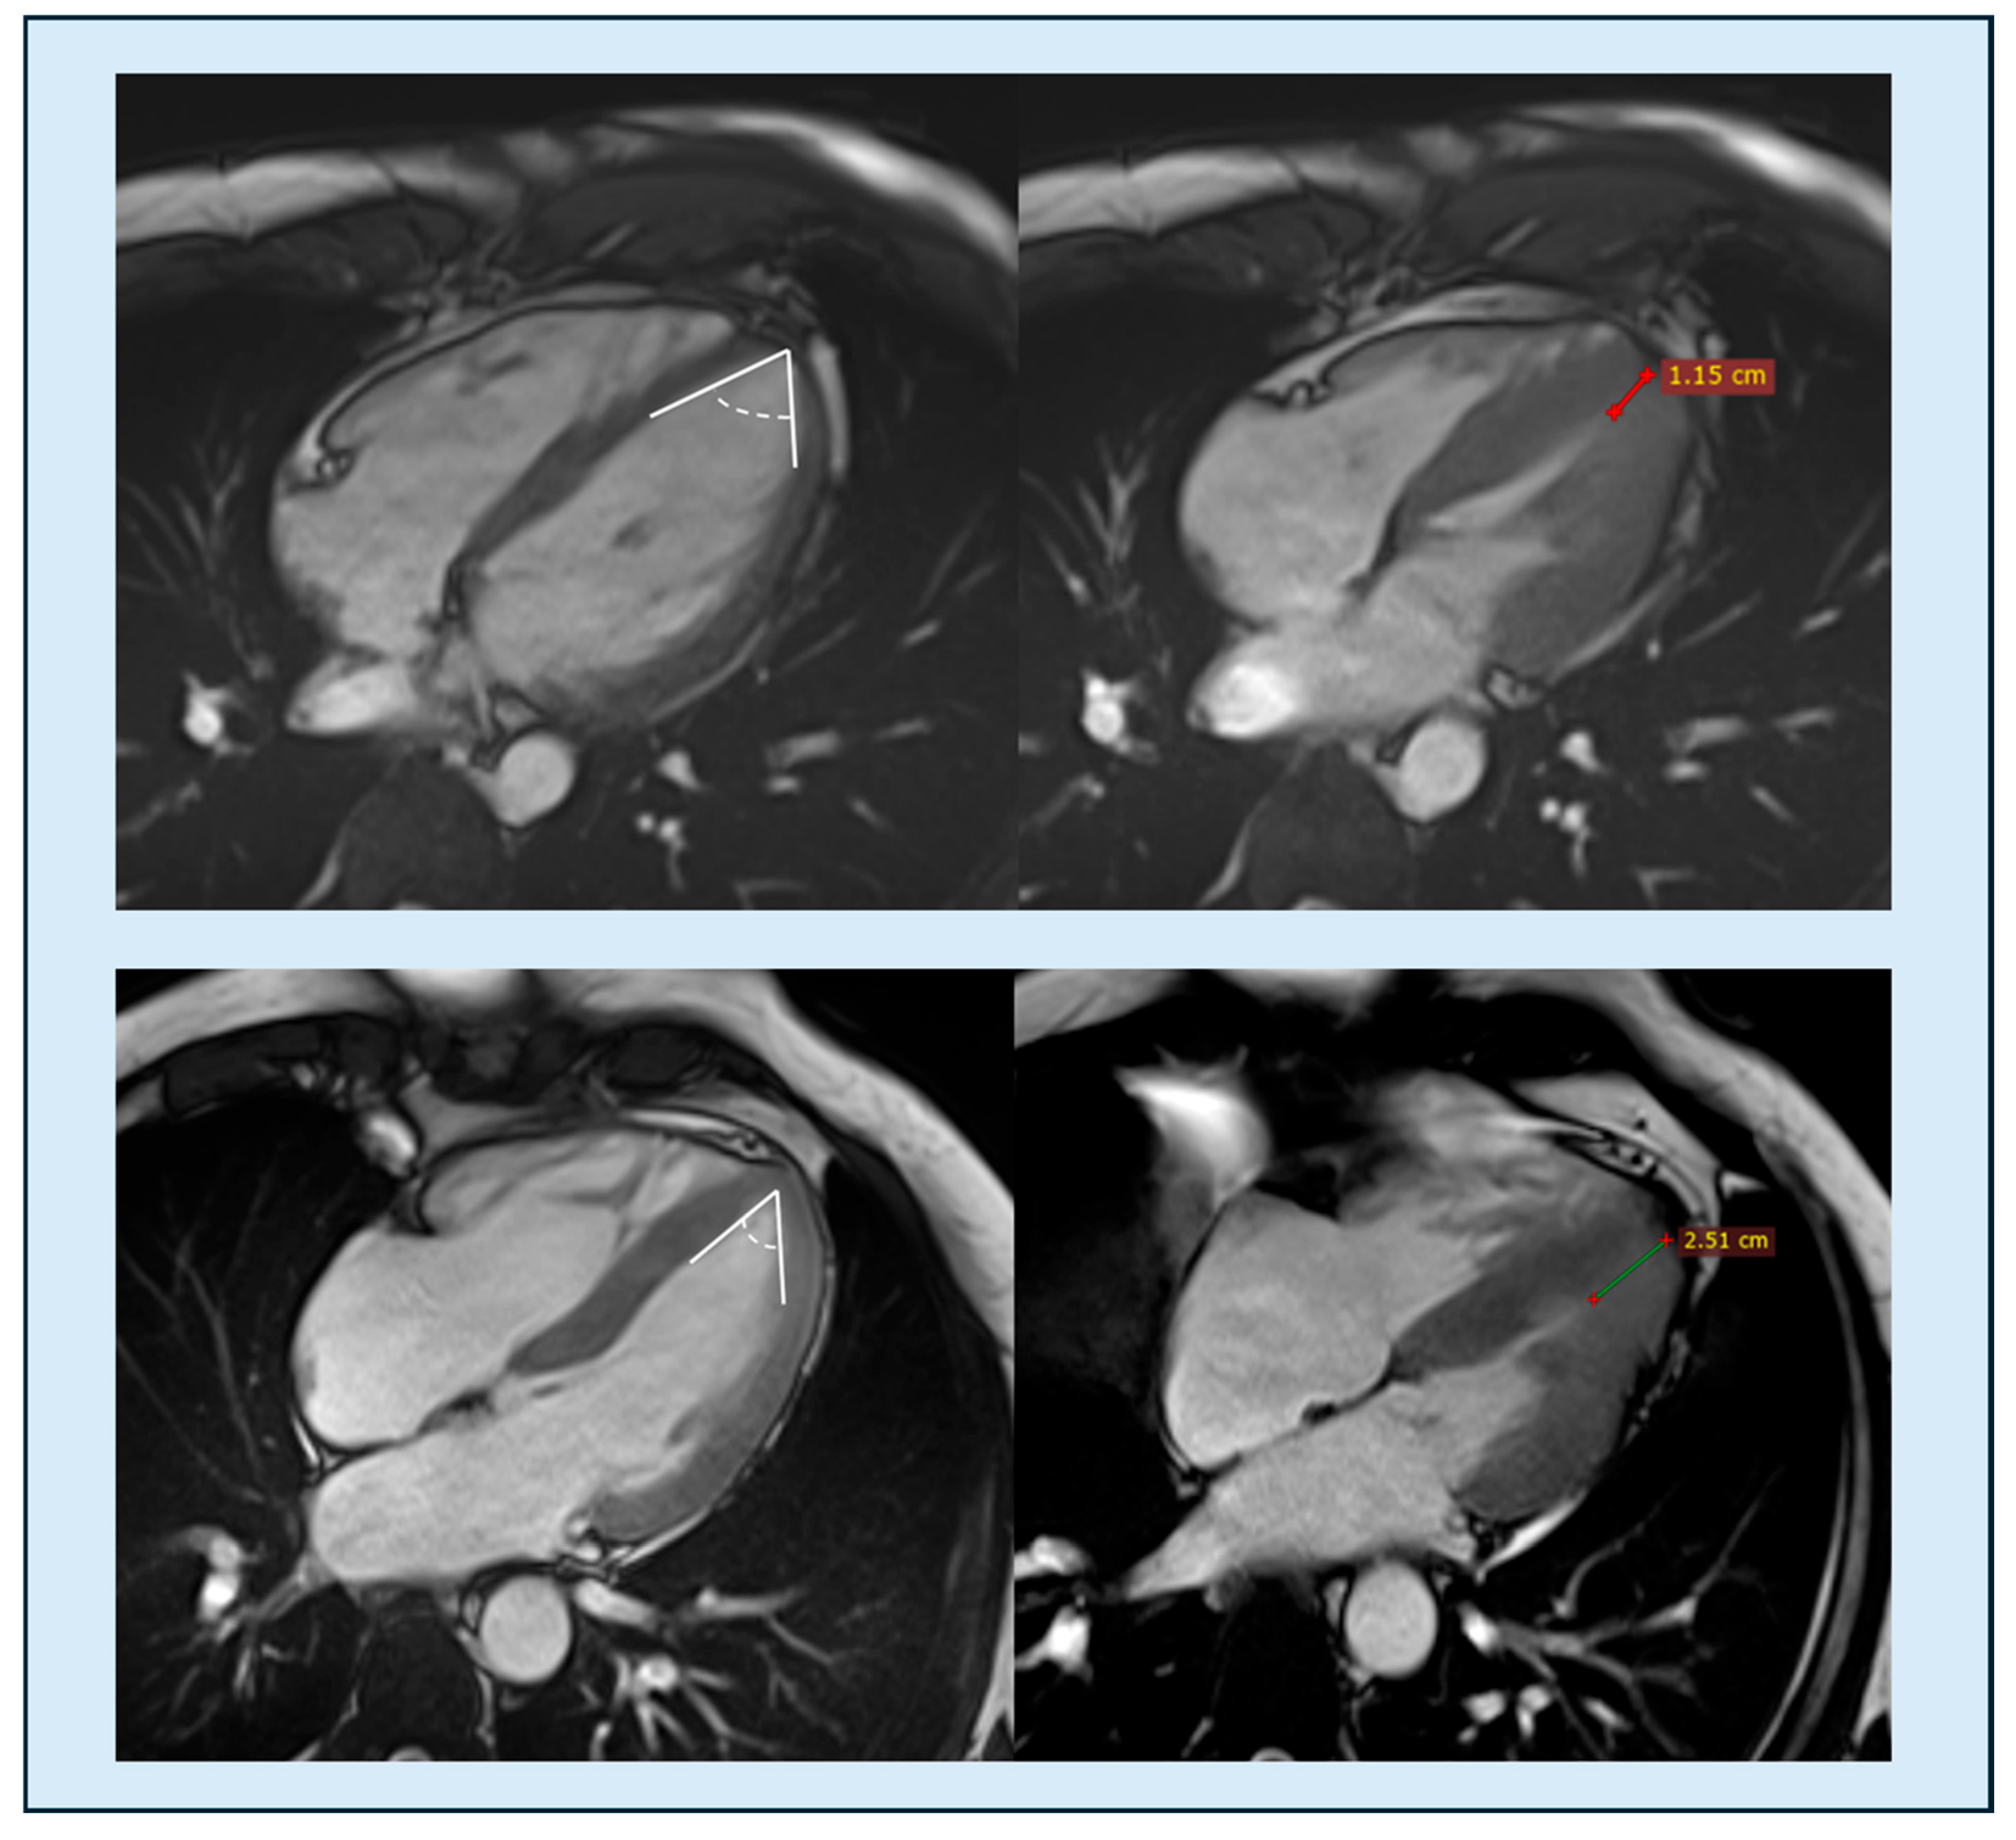

| Apical angle | CMRi | ≤75–76° | 71 pts | AUC 0.77 | Low–mod | ++ | Li 2021 [64] |

| Apical thickness progression | CMRi | Mean ≥7.6 mm; Max ≥9.5 mm | 71 pts | AUC 0.87–0.898 | Moderate | ++ | Li 2021 [64] |